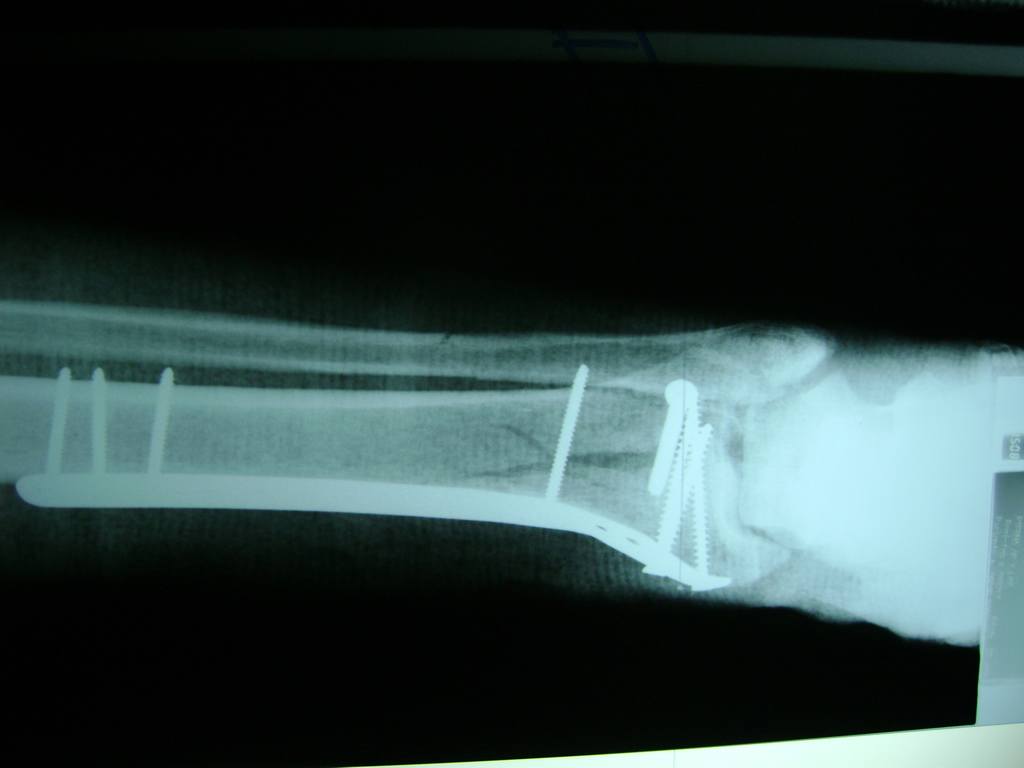

Cirugías de Húmero - Perone y Tibia

Aunque cada uno de estos huesos puede fracturarse por separado, normalmente la rotura es una lesión que se produce de forma conjunta

La mayor parte de las roturas implican a la parte proximal del hueso (parte del hueso próximo a la rodilla) o a la parte distal (parte del hueso cerca del tobillo).

Debido a la fina cobertura de piel que recubre la tibia y el peroné, las fracturas generalmente son abiertas, es decir, el hueso roto rasga la piel, atravesándola. Las fracturas de tibia y peroné generalmente se producen por un fuerte impacto o torsión.